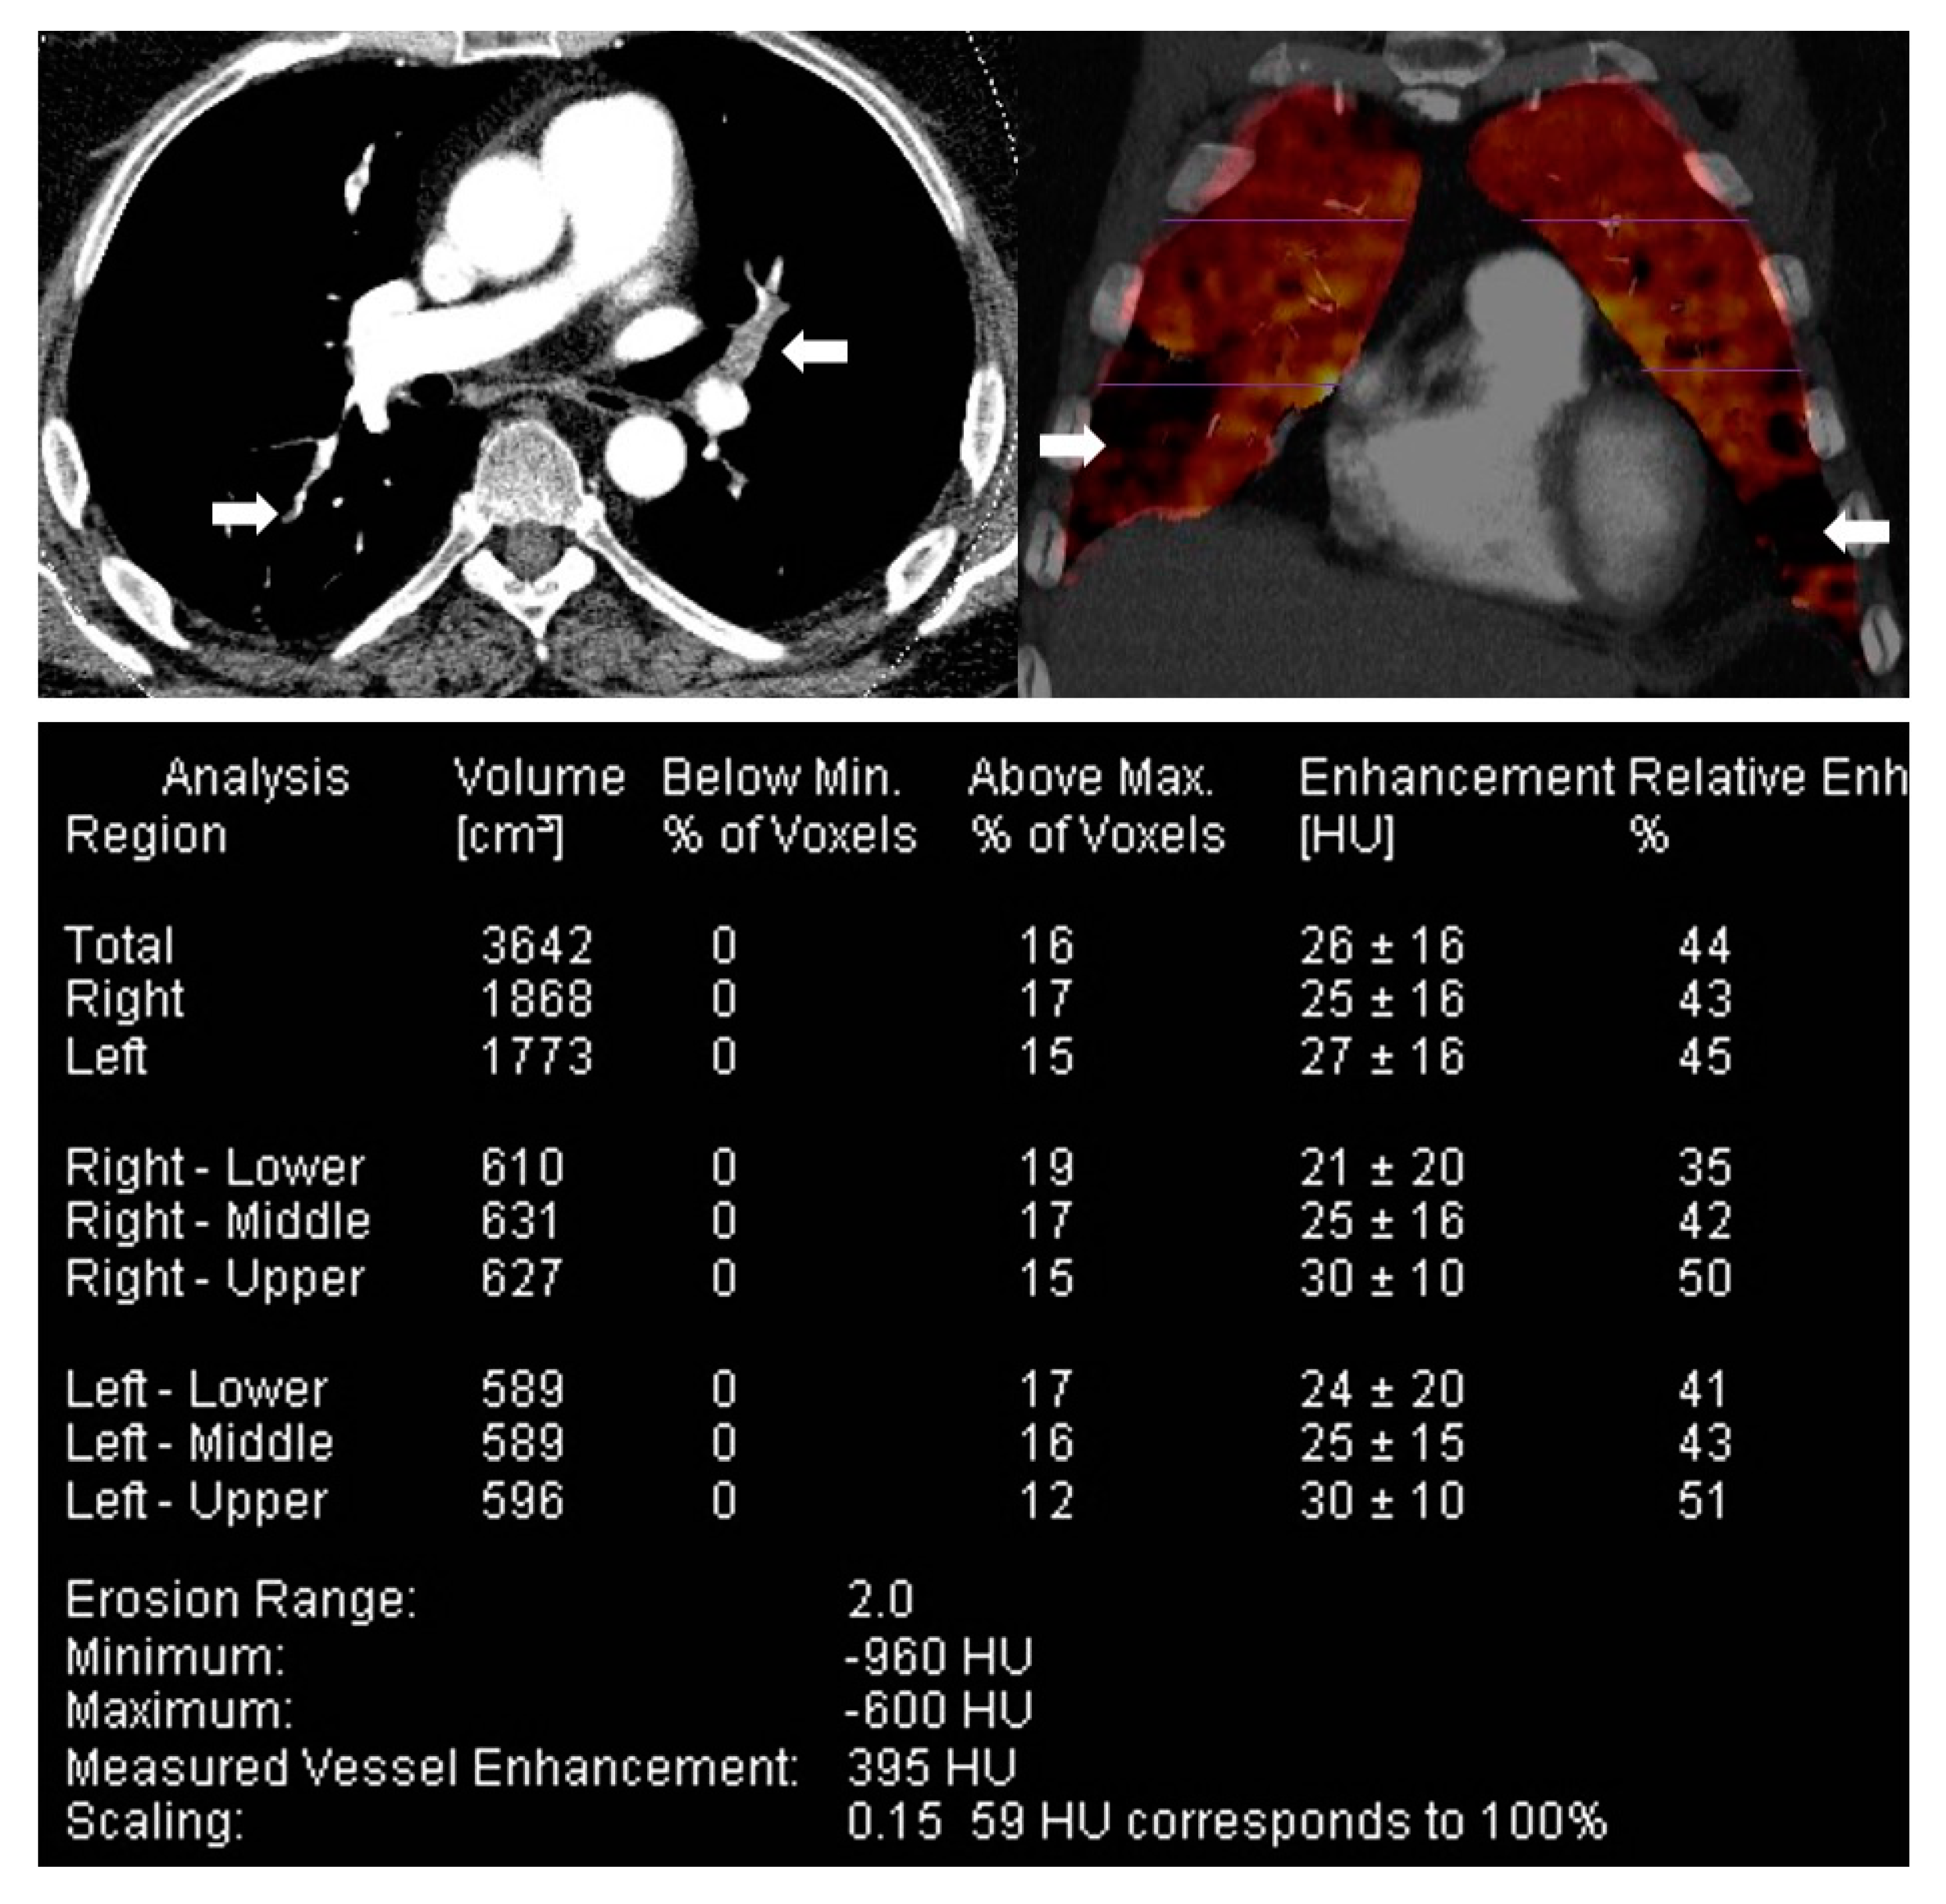

- Pontana, F.; Faivre, J.-B.; Remy-Jardin, M.; Flohr, T.; Schmidt, B.; Tacelli, N.; Pansini, V.; Remy, J. Lung Perfusion with Dual-Energy Multidetector-Row CT (MDCT). Acad. Radiol. 2008, 15, 1494–1504. [Google Scholar] [CrossRef]

- Meinel, F.G.; Graef, A.; Bamberg, F.; Thieme, S.F.; Schwarz, F.; Sommer, W.H.; Neurohr, C.; Kupatt, C.; Reiser, M.F.; Johnson, T.R.C. Effectiveness of Automated Quantification of Pulmonary Perfused Blood Volume Using Dual-Energy CTPA for the Severity Assessment of Acute Pulmonary Embolism. Investig. Radiol. 2013, 48, 563–569. [Google Scholar] [CrossRef] [PubMed]

- Meinel, F.; Graef, A.; Thierfelder, K.; Armbruster, M.; Schild, C.; Neurohr, C.; Reiser, M.; Johnson, T. Automated Quantification of Pulmonary Perfused Blood Volume by Dual-Energy CTPA in Chronic Thromboembolic Pulmonary Hypertension. Fortschr. Röntgenstr. 2013, 186, 151–156. [Google Scholar] [CrossRef]